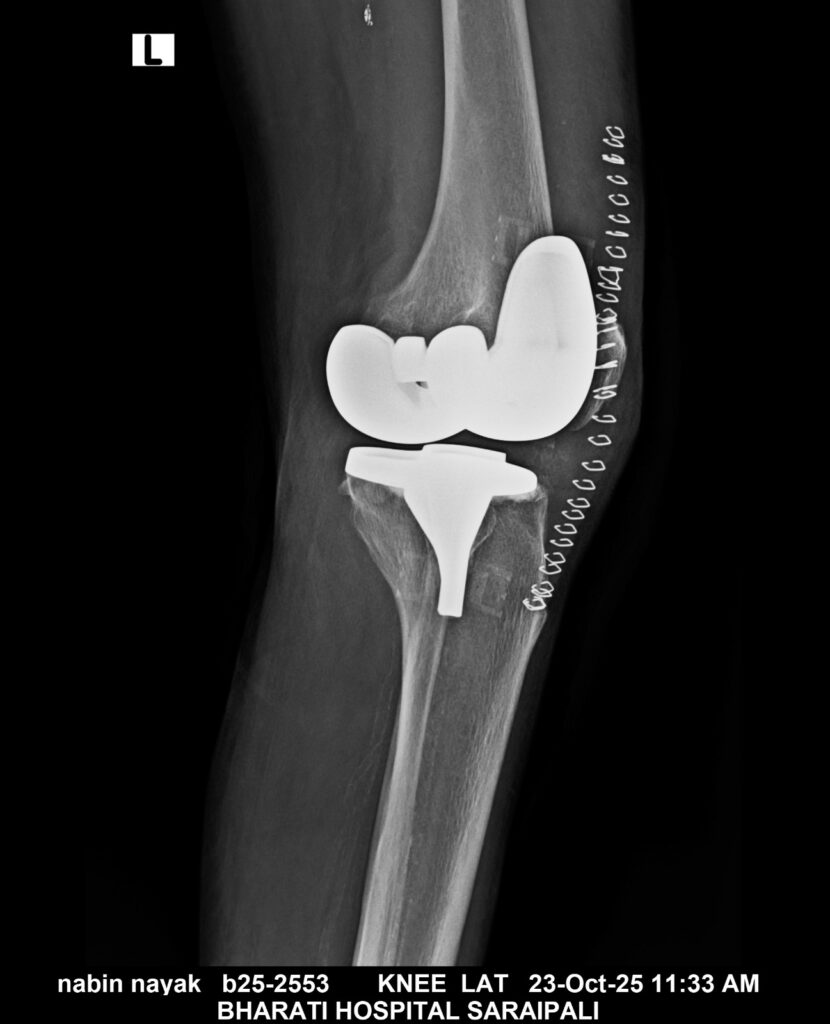

सरायपाली। भारती हॉस्पिटल सरायपाली में अब घुटने के समस्या के लिए रायपुर, विशाखापट्टनम जैसे बड़े शहरों की और जाने की कोई आवश्यकता नहीं। विगत कुछ वर्षों से एक 70 वर्षीय वृद्ध व्यक्ति बहुत दिनों से घुटने के दर्द से परेशान था और चलने फिरने में भी उनको बहुत तकलीफ होती थी।

किन्तु जब उन्होंने ईलाज के लिए भारती हॉस्पिटल में आए। इसके पश्चात् यहां पर उनका ईलाज संभव हो पाया। इस प्रत्यारोपण को डॉ सौरभ खरे और डॉ त्रिपाठी के द्वारा सफलतापूर्वक किया गया।